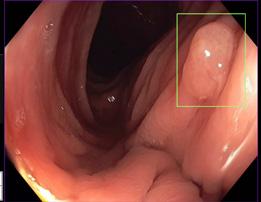

Figur 1. MR- og ultralydbilde av ADPKD nyrer. A) Koronalplan av T2-vektet MR bilde som viser lengde og bredde av nyrene hos en ADPKD pasient. B) Aksialplan av T2-vektet MR bilde av samme pasient hvor også en del levercyster er synlig øverst i bildet. C) Ultralydbilde som viser cyster med tynne septa (hvit på bildet) og væskefylt innhold (svart på bildet). Bruk av MR- og ultralydbilder fra denne pasienten er godkjent av pasienten etter innhentet samtykke (Ø. Eikrem).